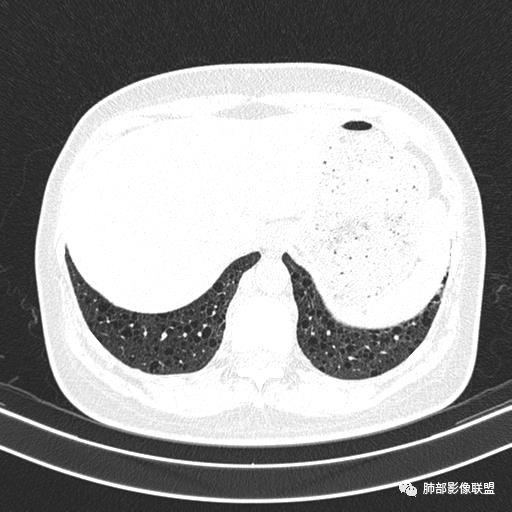

双肺弥漫囊腔,累及肋膈角,囊腔形态相对规则单一。

女,46,活动性气喘1年。苯吸入史半年。胸部CT:两肺弥漫囊腔,上至肺尖,下至肋膈角,形态类似小囊腔。考虑:LAM,鉴别LIP,BHD,PLCH等。

CT表现:双肺弥漫大小不等的薄壁囊腔,囊壁<2mm,外形规则,血管影多位于囊腔周围,囊腔之间肺组织正常,随着疾病进展到晚期,囊腔变大、增多,不可胜数,囊腔可融合成较大的囊,与肺气肿相似,形成间质性肺纤维化。部分病例可出现结节影。